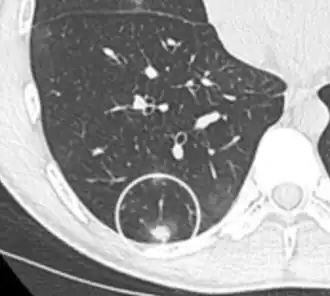

Lung nodule abutting a pulmonary cyst.[9]

• A lung nodule abutting a pulmonary cyst is a rare finding, yet indicating cancer.[9]